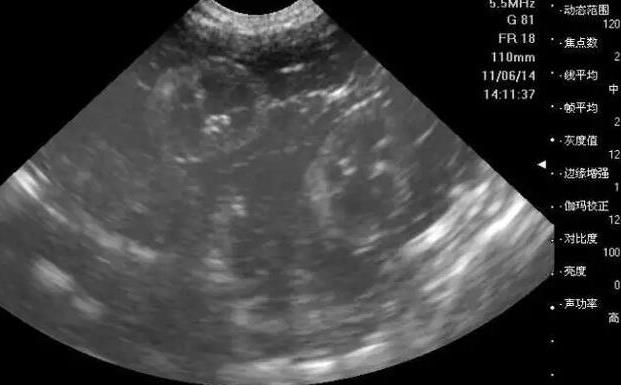

3. 卵泡监测:在促排卵治疗期间,医生会通过超声波监测女性的卵泡情况,以确定最佳的取卵时间。